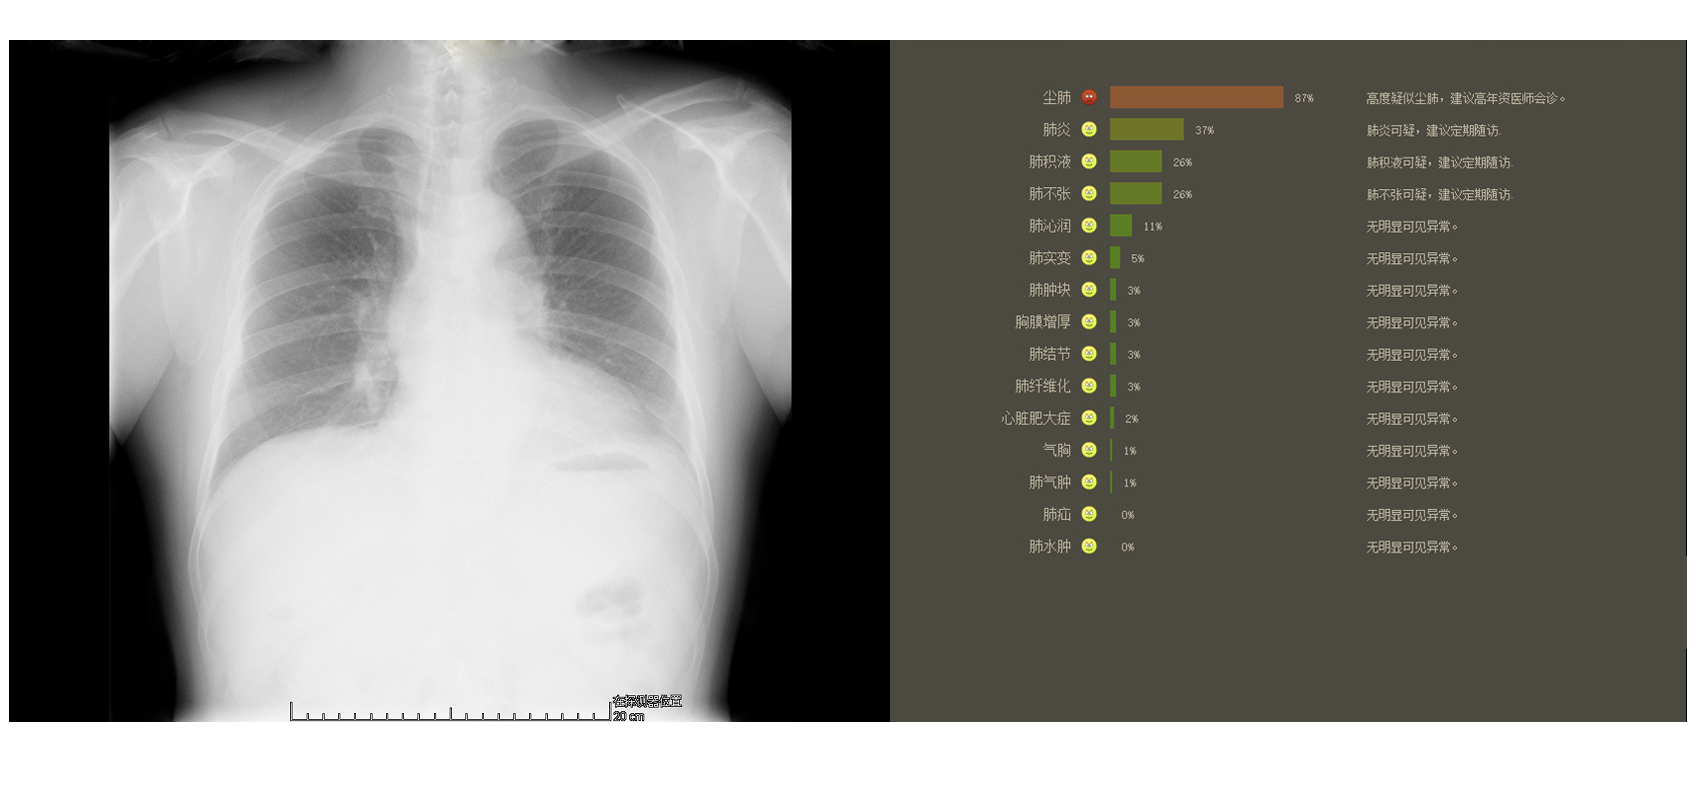

DR胸片智能筛查

对尘肺、肺不张、心脏肥大症、肺积液、肺沁润、肺肿块、肺结节、肺炎、气胸、肺实变、肺水肿、肺气肿、肺纤维化、胸膜增厚、肺疝,共15种常见肺病进行自动判断,辅助医生迅速筛检出存在病灶的影像,提高筛查效率,降低漏诊率。